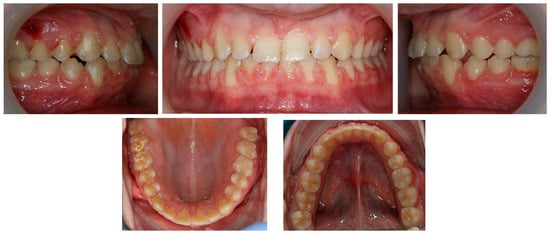

Figure 3. Pre-treatment panoramic radiograph.

Panoramic radiography, performed in 28 November 2018 (Densply Sirona, Charlotte, NC, USA, Orthophos SL 2D), revealed a full dentition and shortened tooth root length: 24, 25, 31, 32, 33, 34, 35, 41, 42, 43, 44, 45. The X-ray is presented in Figure 3.